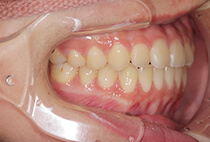

治療前

治療後

八重歯の見た目が気になってご来院されましたが、実は顎の痛みや開口障害など、顎関節症の症状もありました。

そのため、かみ合わせと顎関節症の治療を同時に行ったにもかかわらず、2年間で治療が終了。

かみ合わせが整い咬筋の過緊張も改善しました。咬筋の肥大も治ってフェイスラインがすっきりしました。

最終的には美しい歯並びと、安定した痛みのないかみ合わせが実現しました。

しっかり前歯を下げるために、インプラントアンカーを使用してコントロールしました。

かみ合わせが整うと咬筋の過緊張が改善。

過緊張による筋肉肥大も改善しフェイスラインもすっきりしました。